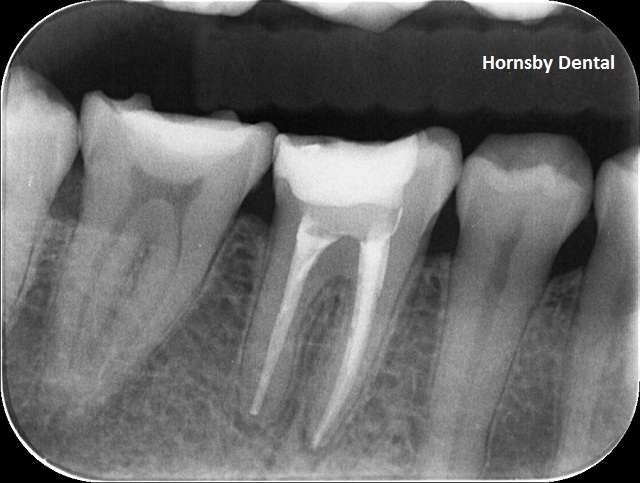

POST-OP

Post-op: A well-obturated/filled root canal therapy. The tooth is symptom-free and will have a crown placed on it to seal the tooth from any potential fracture and decays in it. Studies have shown a well-placed dental crown can provide superior seal and, if possible, should always be placed on the tooth after the root canal therapy is completed with the tooth being symptom-free.